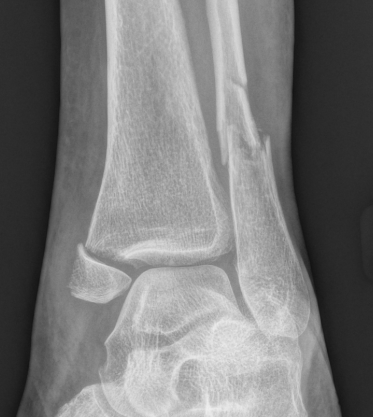

X-ray assessment

3 standard views

AP / Lateral / Mortise

Mortise

- AP with foot internally rotated

- should be symmetrical space around talus

Ankle Mortise ViewMortise

Increased tibio-fibular clear space  Overlap Increased medial clear space

Medial border of the fibula

Lateral border of the posterior tibia (incisura fibularis)

Measured 1 cm above the plafond

Overlap of the fibula and the anterior tibial tubercle

Medial talus to lateral medial malleolus

<5mm AP and mortise

> 6 mm AP view

> 1 mm mortise view

< 4mm

Equal to superior clear space

Syndesmotic injury Syndesmotic injury

Deltoid ligament injury

Lateral talar shift

Ankle AP Xray Syndesmotic Measurements Ankle Mortice Xray Syndesmotic Measurements Mortise